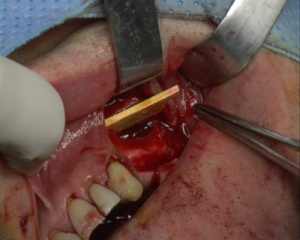

Ce film présente un comblement bilatéral sinusien pré-implantaire. Il y est présenté l'utilisation d\'une lame de phosphate tricalcique de type "sinus up"

Photos extraites de la vidéo :